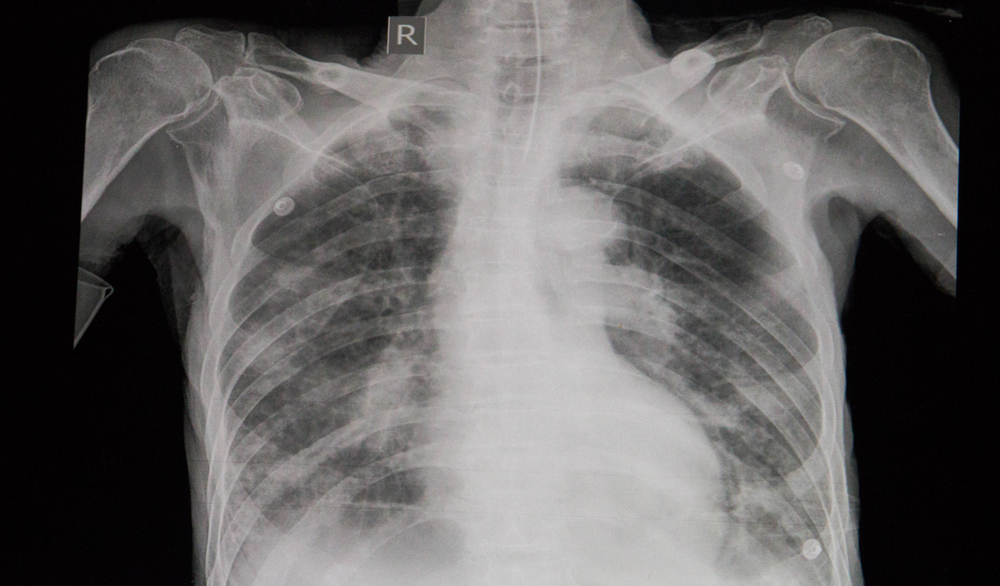

Mas nem todo edema pulmonar vem do coração. Existe o tipo não cardiogênico, desencadeado por lesões diretas nos pulmões, como pneumonia grave, inalação de fumaça, afogamento ou até mesmo altitudes elevadas (conhecido como HAPE). Os sintomas são dramáticos: falta de ar intensa que piora ao deitar, tosse com expectoração espumosa ou rosada, sensação de sufocamento, pele fria e úmida, e ansiedade extrema. O diagnóstico é feito rapidamente no hospital com raio-X de tórax e exames de sangue, e o tratamento imediato inclui oxigênio e diuréticos potentes, como a furosemida, para eliminar o excesso de líquido.

O diagnóstico de edema pulmonar é essencialmente clínico, baseado na história do paciente e nos sintomas apresentados. O médico experiente consegue suspeitar do quadro pela descrição da falta de ar e outros sinais clássicos. Exames complementares ajudam a confirmar e a identificar a causa.

O raio-X de tórax é fundamental para visualizar o acúmulo de líquido. Um eletrocardiograma (ECG) pode indicar problemas cardíacos subjacentes, como a insuficiência cardíaca. Em alguns casos, exames de sangue e ecocardiograma podem ser necessários para uma avaliação completa.